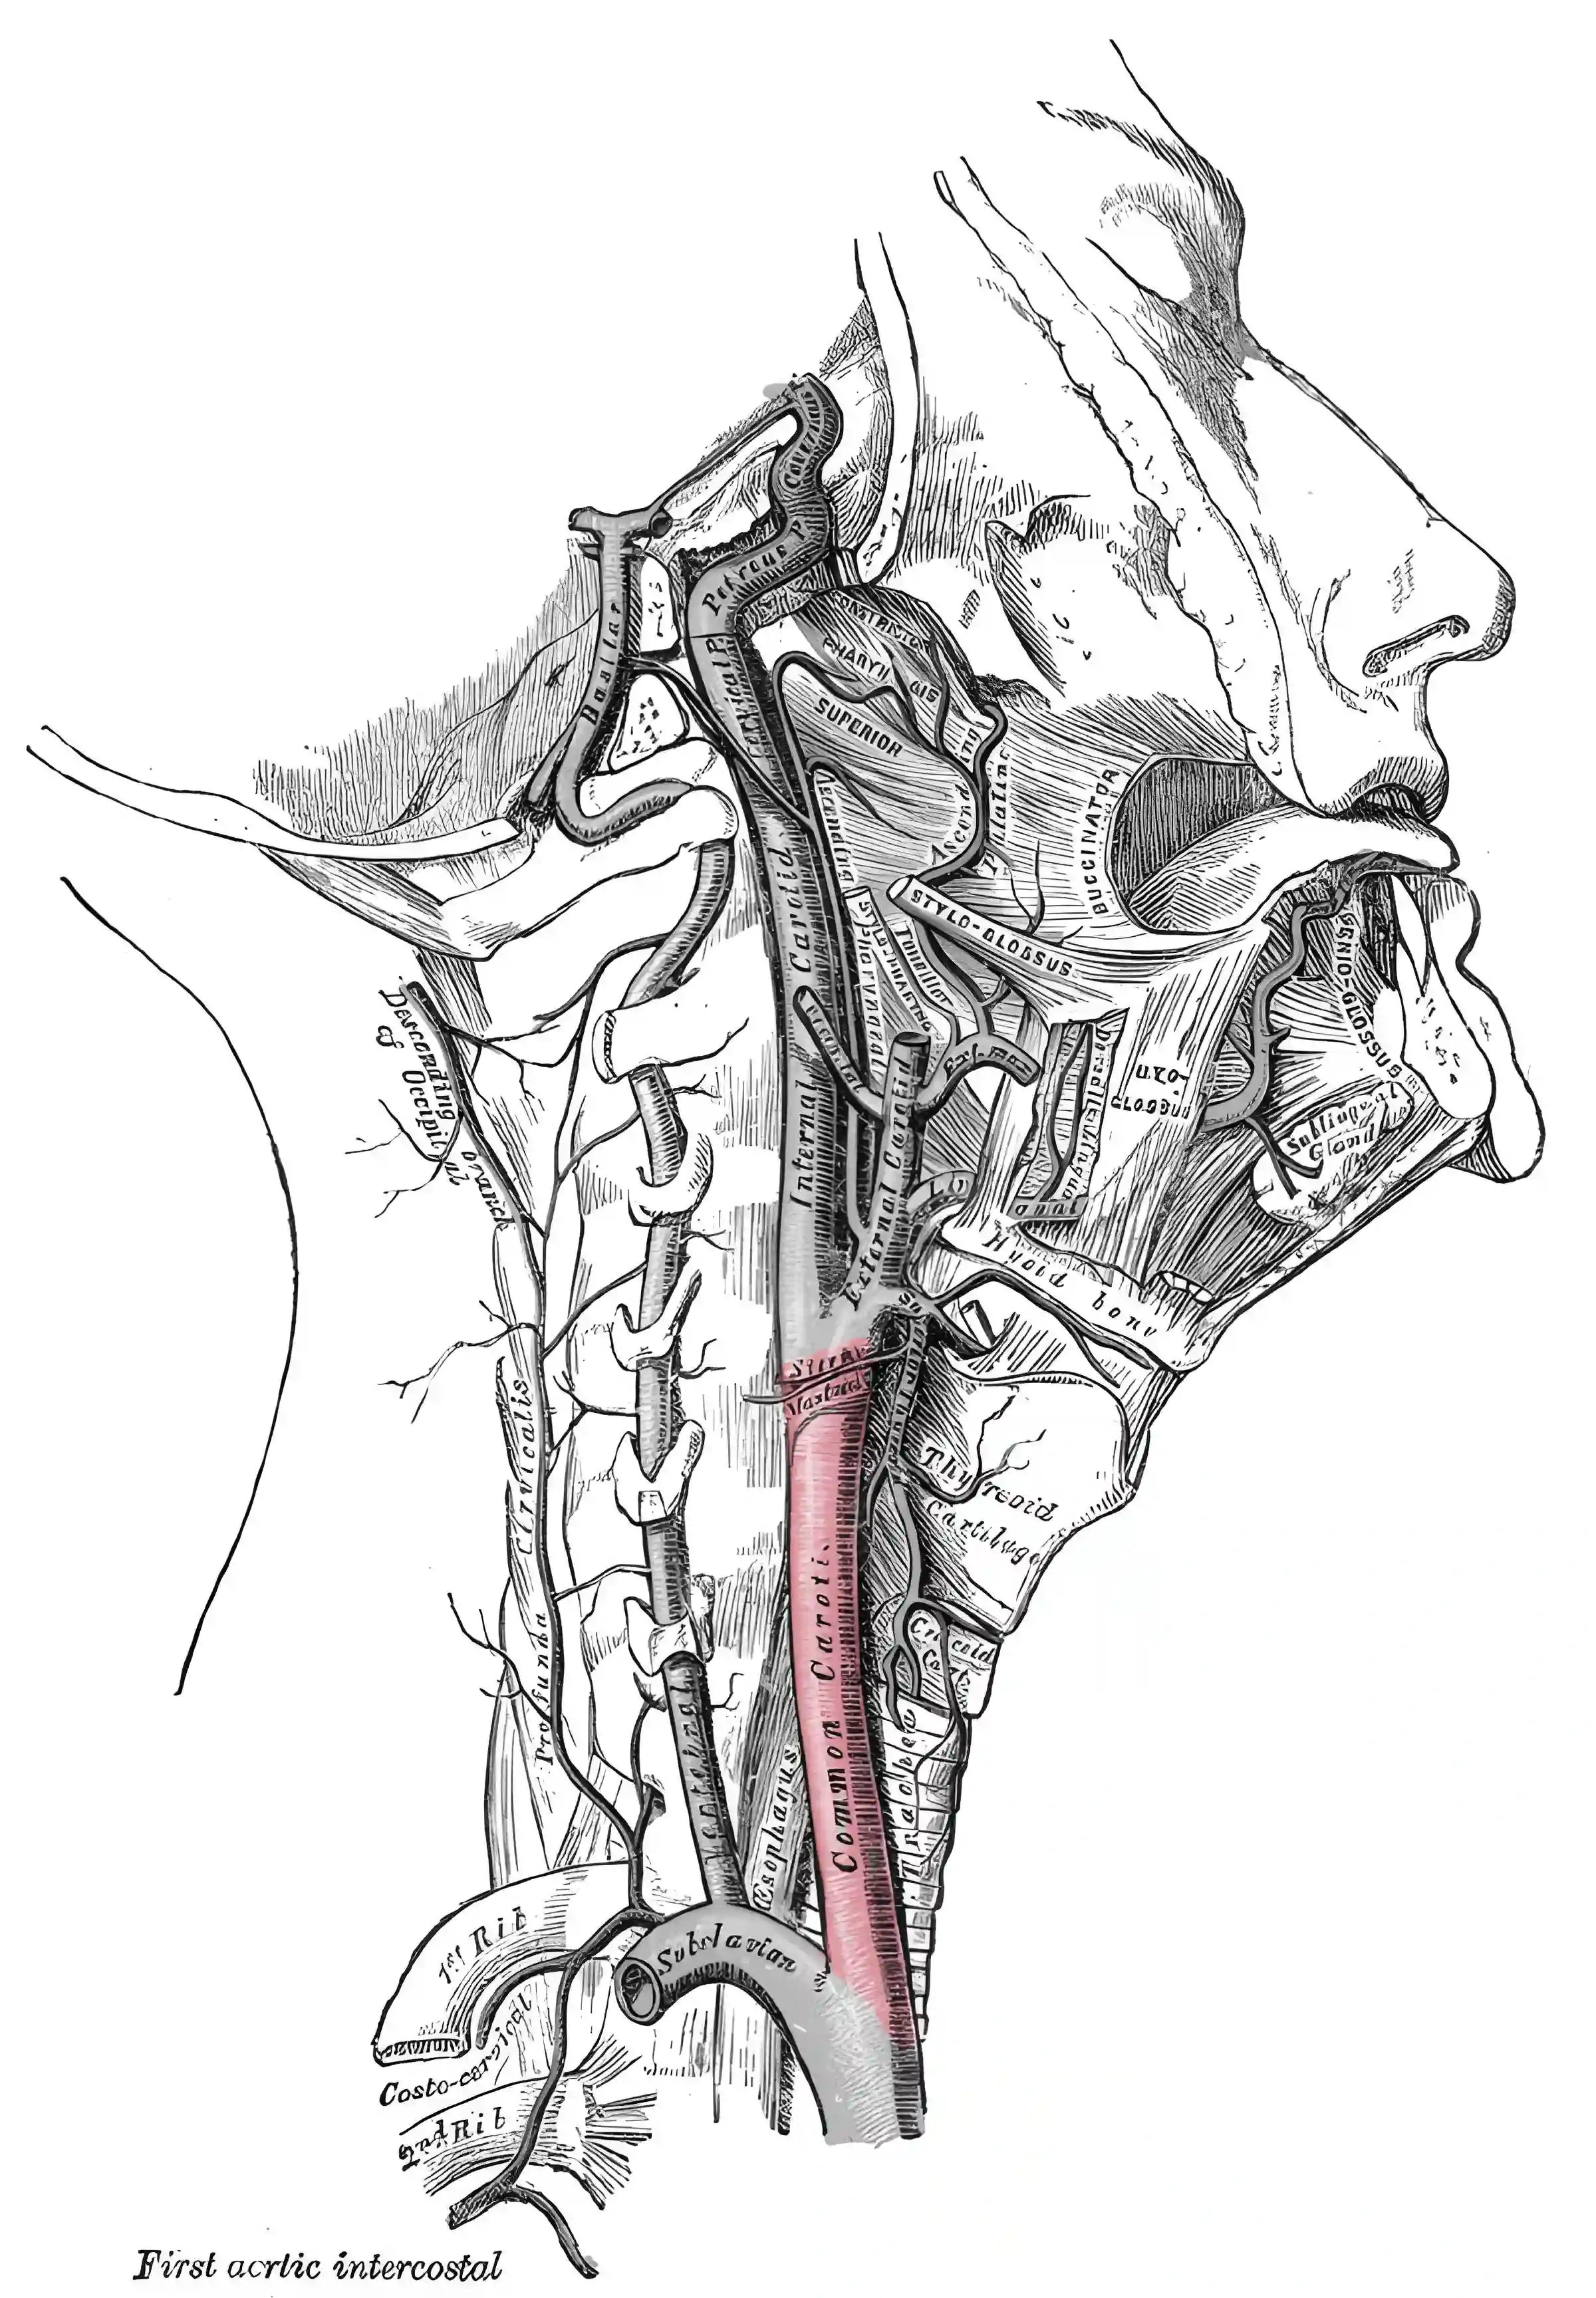

Abbildung

Schematische Darstellung der rechten Arteria carotis communis. Abbildung adaptiert von Grays Anatomy Figure 513.